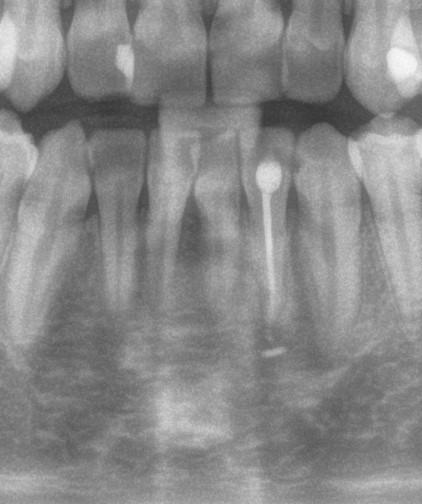

2. ábra: A páciens számára a kezelés minden szakasza során bemutatásra kerülnek az intraorális szkenner segítségével készült felvételek. 3. ábra: Radiológiai felvételek. – 4. ábra: Parodontális szondával történő tasakmérés. 5. ábra: Egy háromdimenziós modell segítségével megfelelő információkkal látjuk el és motiváljuk a pácienst.

Az első találkozás alkalmával a kezelést igénylő terület állapotát egy intraorális szkenner segítségével rögzítjük. Ez a képalkotó eljárás kiegészíti azokat az általánosan alkalmazott vizsgálatokat, mint a radiológiai képalkotás (3. ábra) és a parodontális státuszfelvétel (4. ábra), továbbá hozzájárul a pontos diagnózis felállításához.

A 10 éves férfi páciens a felső frontfogai késői/nem megvalósuló előtörése miatt kereste fel a rendelőnket. A klinikai és a radiológiai vizsgálat során a jobb felső nagymetszőfog impakcióját észleltük (1. ábra). A fog horizontális tengelyállással és dilacerált gyökérrel rendelkezett. A felső dentális középvonal a fogak vándorlása miatt jelentős mértékben elcsúszott. A bal felső kismetszőfog is rendkívül kedvezőtlen pozícióba került.

Dr. Kazem Dalaie, dr. Samin Ghaffari, dr. Mazir Mir (Irán, Németország) 1. a ábra: Az intraorális felvételen jól látható a jobb felső nagymetszőfog lehetséges impakciójára utaló foghiány.

1. b ábra: A panoráma röntgenfelvételen megfigyelhető a teljes impakcióban lévő jobb felső nagymetszőfog. 1. c ábra: A CBCT felvétel is igazolja a jobb felső nagymetszőfog impakcióját.